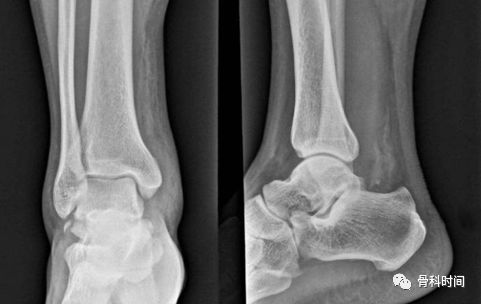

强直性脊柱炎有什么影像学表现?

X 线检查对 AS 的诊断有极为重要的意义,早期几乎都有骶髂关节炎表现,病变一般在骶髂关节的中下部开始,为两侧性。

开始多侵犯髂骨侧,进而侵犯骶骨侧。可见斑点状或块状,髂骨侧明显,继而侵犯整个关节,边缘呈锯齿状,软骨下有骨硬化,骨质增生,关节间隙变窄,最后关节间隙消失,发生骨性强直。

脊柱病变的 X 线表现早期为普遍性骨质疏松,椎体呈「方形椎」,最典型的表现是「竹节样改变」,T10-L2 较常见,腰椎呈「鱼尾椎」改变。